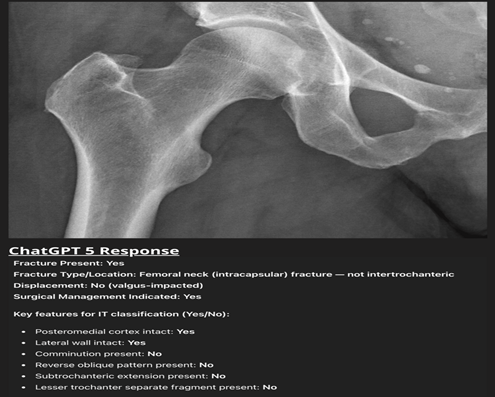

In contrast, for the IT femur group (n = 60; 48 fractures, 12 normal), ChatGPT-5 detected all 48 fractures (100% sensitivity) but overcalled 10 of 12 normals as fractured, yielding specificity 16.7%, accuracy 83.3%, and κ = 0.24 (fair agreement). The model’s tendency to hallucinate was highlighted by a case in which it identified a “displaced femoral neck fracture with varus angulation” on a normal hip X-ray despite no visible fracture line or trabecular disruption, exemplifying the model’s propensity for hallucination (Fig. 2).

Figure 2: Normal anteroposterior hip radiograph that ChatGPT-5 misinterpreted as a “valgus-impacted femoral-neck fracture.” Despite intact cortical outlines and an undisturbed trabecular pattern, the model reported a displaced intracapsular fracture requiring surgery, illustrating its tendency toward false-positive fracture detection and poor specificity in the intertrochanteric group.